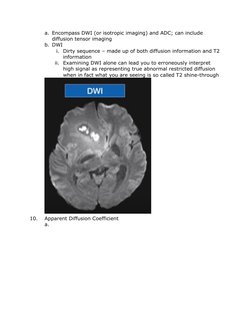

9. Diffusion weighted imaging

a. Encompass DWI (or isotropic imaging) and ADC; can include

diffusion tensor imaging

b. DWI

i. Dirty sequence made up of both diffusion information and T2

information

ii. Examining DWI alone can lead you to erroneously interpret

high signal as representing true abnormal restricted diffusion

when in fact what you are seeing is so called T2 shine-through